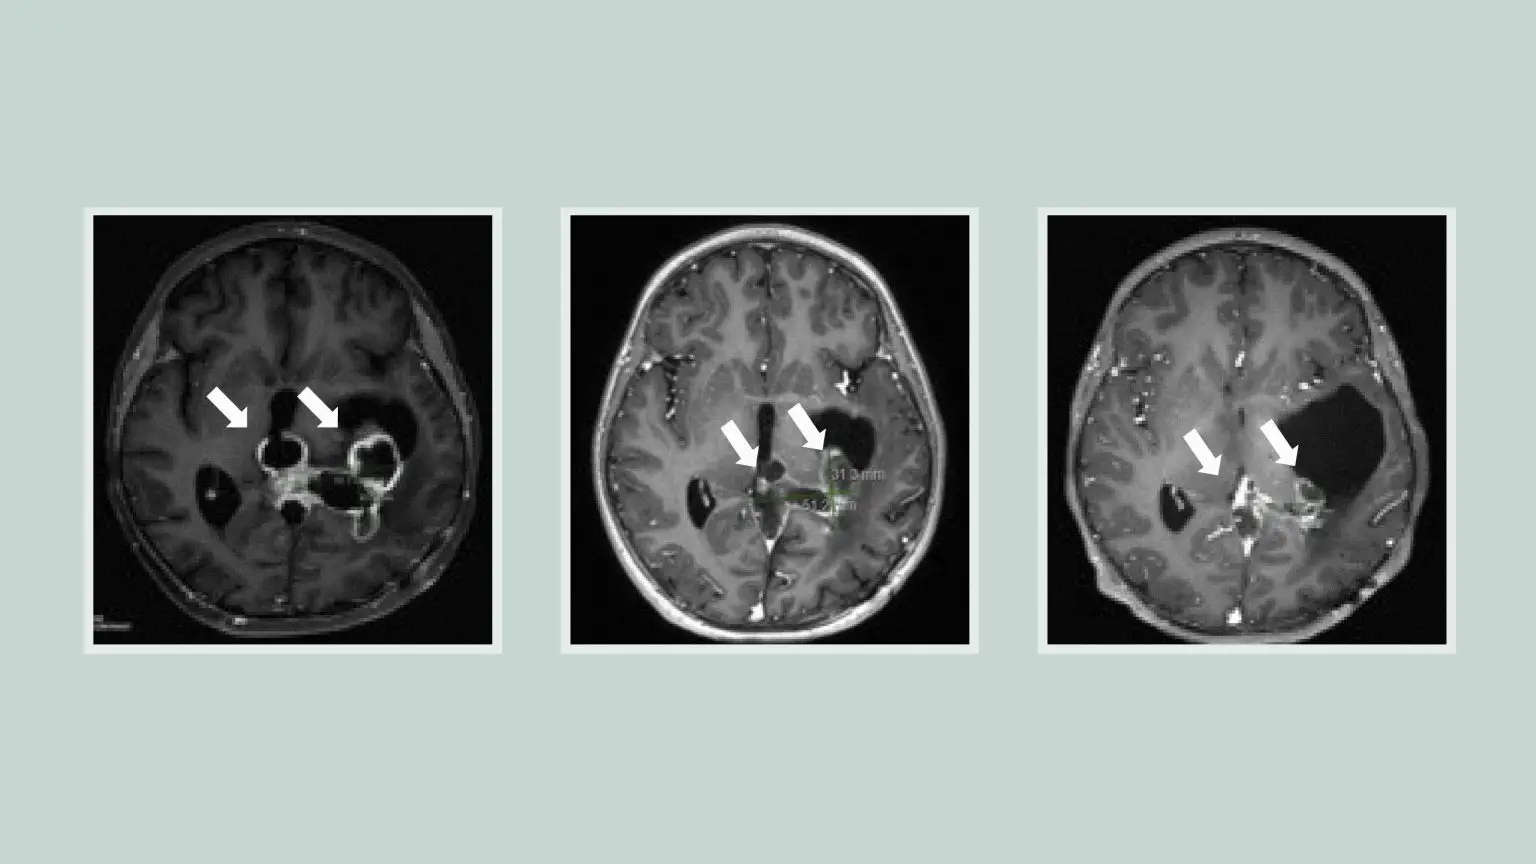

一系列脑部扫描显示肿瘤对ONC201的反应正在缩小。资料来源:密歇根医学院

在对71名H3K27M突变的弥漫性中线胶质瘤患者进行的两项临床试验中,入组时未复发的肿瘤患者的中位总生存期接近22个月,近三分之一的患者存活时间超过两年。